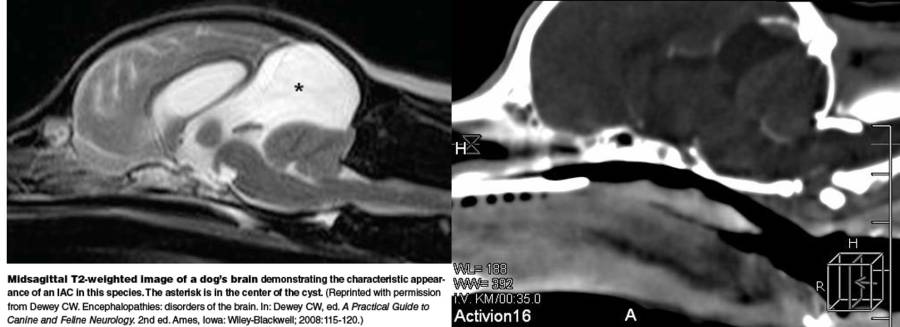

- quadrigmenale subarachnoidale Zyste

- intrakranielle subarachnoidale Zyste